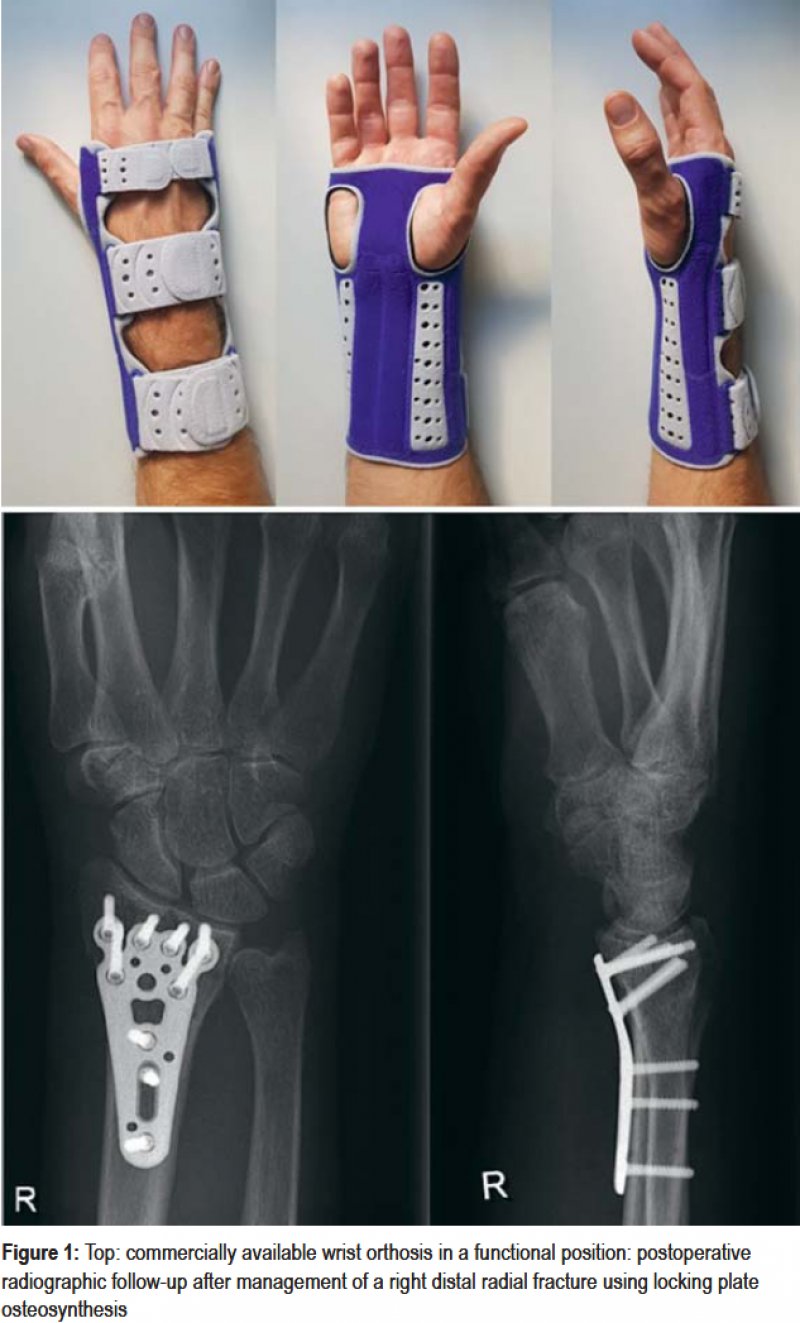

Early Mobilization Versus Splinting After Surgical Management of Distal

From www.aerzteblatt.de

Early Mobilization Versus Splinting After Surgical Management of Distal Wrist Splint Distal Radius Fracture Describe the presentation of a patient with distal radius fracture. Distal radius fractures are the most common orthopaedic injury and generally result from fall on an outstretched hand. It is a break in one of the long forearm bones (radius) at your wrist, you can also break the ulna at the. Review the causes of distal radius fracture. If the. Wrist Splint Distal Radius Fracture.